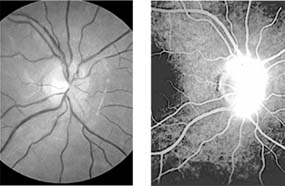

Without treatment, vision characteristically begins to improve 2-3 weeks after onset and sometimes returns to normal within a few days. Improvement may continue slowly over many months, with recovery to 20/40 or better occurring in over 90% of cases at 1 year from onset. Poorer vision during the acute episode is correlated with poorer visual outcome, but even loss of all perception of light can be followed by complete return of vision. A poor visual outcome is also associated with longer lesions in the optic nerve, especially if there is involvement of the nerve within the optic canal. In general there is close correlation between recovery of visual acuity, contrast sensitivity, and color vision. If the disease process is sufficiently destructive, retrograde optic atrophy results, nerve fiber bundle defects appear in the retinal nerve fiber layer (Figure 14-11), and the disk loses its normal pink color and becomes pale. In very severe or recurrent cases, a chalky white disk with sharp outlines results, though disk pallor does not necessarily correlate with poor visual acuity.

Figure 14-11

Figure 14-11: Retinal nerve fiber layer in demyelinating optic neuropathy of multiple sclerosis. The upper temporal nerve fiber bundles show multiple slit-like areas of thinning (arrows) representing retrograde axonal atrophy from subclinical disease in the optic nerve. Vision in the eye was 20/20.

Intraocular inflammation is associated with multiple sclerosis, particularly subclinical peripheral retinal venous sheathing, which can be highlighted by fluorescein angiography.